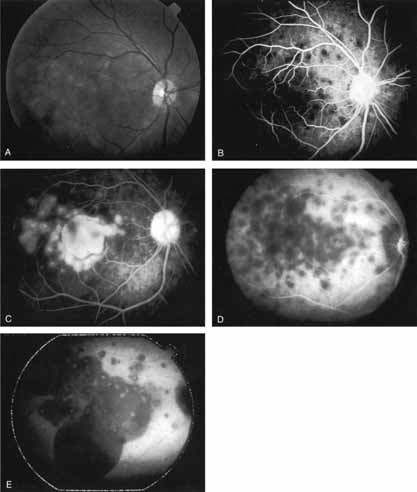

Fig. 11 A. Clinical photograph of a patient with retinal angiomatous proliferation (RAP). There is a hemorrhage with a retinal pigment epithelial detachment. B. Early-phase fluorescein angiogram demonstrates the retinal–retinal anastomosis. C. Late-phase fluorescein study demonstrates the late-staining hyperfluorescence seen in RAP lesions with a hyperfluourescent retinal pigment epithelial detachment. D. Mid-phase indocyanine green study demonstrates the hyperfluorescent hot-spot overlying the hypofluorescent retinal pigment epithelial detachment. E. Late-phase ICG angiogram demonstrates late hyperfluorescent leakage (CME) into the retina.

ICG angiograms of RAP lesions reveal a focal area of intense hyperfluorescence corresponding to a so-called hot-spot of neovascularization with some late extension of the leakage within the retina caused by intraretinal neovascularization (IRN) within the deep layers of the retina. As the IRN progresses down into the subretinal space, the neovascularization present in the choroid joins the IRN to form a large, neovascular complex. At this stage, clinical and angiographic evidence of a vascularized PED (V-PED) is often present. ICG is the preferred method of imaging a V-PED because the serous component of the PED remains hypofluorescent while the vascular component displays hyperfluorescence. ICG angiography may be able to capture direct communication between the retinal and choroidal component of the neovascular complex as they meet to form a retinal choroidal anastomosis (RCA).34 Treatment options of RAP lesions include: traditional laser photocoagulation of the stage 1 and early stage 2 lesions, surgical excision of stage 2 lesions in conjunction with laser diathermy, as well as PDT, alone and in combination with other treatments, particularly triamcinolone acetonide.36,37 Other therapies, both singly and in combination, are currently undergoing investigation for this unique form of neovascular AMD.